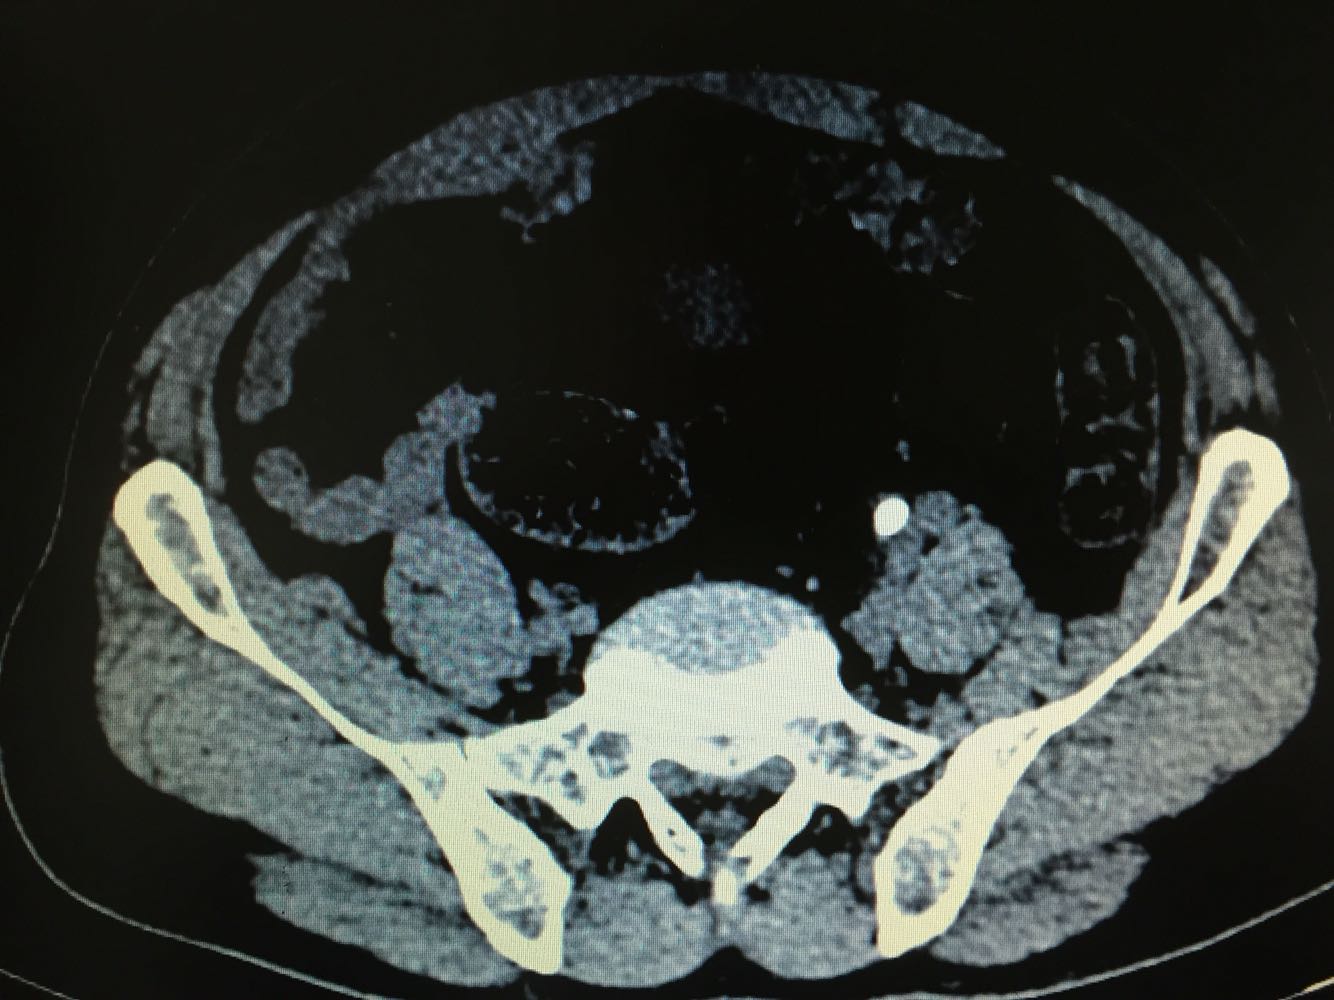

双侧输尿管结石

体检发现双侧输尿管结石,双肾积水1周,尿量无明显变化

双侧输尿管结石,双肾积水

治疗方案,拟先行左侧输尿管镜下碎石,再行右侧输尿管软镜下碎石术。